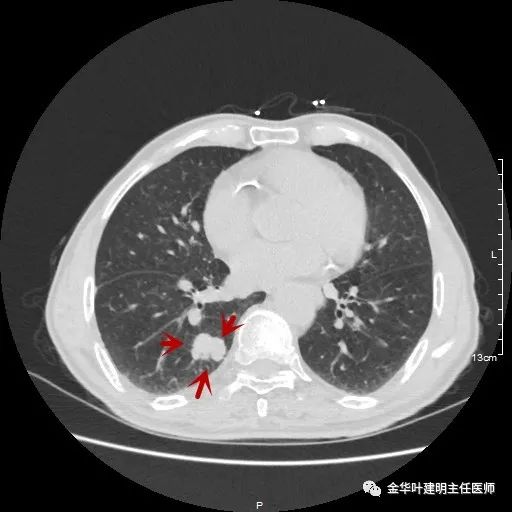

金华的某A,今年已经80岁了,前些天检查发现右下肺部占位,让我会诊。我打开电脑一看图,发现右下肺是典型的实性分叶状的占位,基本可肯定肺癌,余肺仍有多处磨玻璃影及类似慢性炎的病灶,是不是合并炎症?还是多原发肺癌?鉴于其中叶肺门部混合磨玻璃结节边缘略显模糊,为了防止炎性病灶,让其进行了10天的静脉抗炎治疗,但复查靶扫描后发现病灶无任何吸收好转,靶扫描上把细节显示的更清楚了,反而更坚定了我判断其为肺癌的结论。对于这样年纪的多原发癌,我们该如何来进行临床思考呢?治疗该如何建议与决策?当然最后的结果要如实告知患方后,由他们自己决定。

以上示右肺中叶病灶3。是混合磨玻璃结节,位置差,邻近肺门部,无法局部楔形切除,抗炎治疗后靶扫描显示了更清楚的细节,是典型的肺癌影像特征(此处未另提供)。从单病灶来看,需要行右肺中叶切除并清扫淋巴结才能得以治疗。

以上示右中叶病灶4。也是囊腔型病灶,病灶大,囊壁是磨玻璃密度,亦是较为典型的囊腔型肺癌影像。单病灶看,需中叶切除来治疗,因病灶3的存在,中叶切除可同时解决病灶3与病灶4。